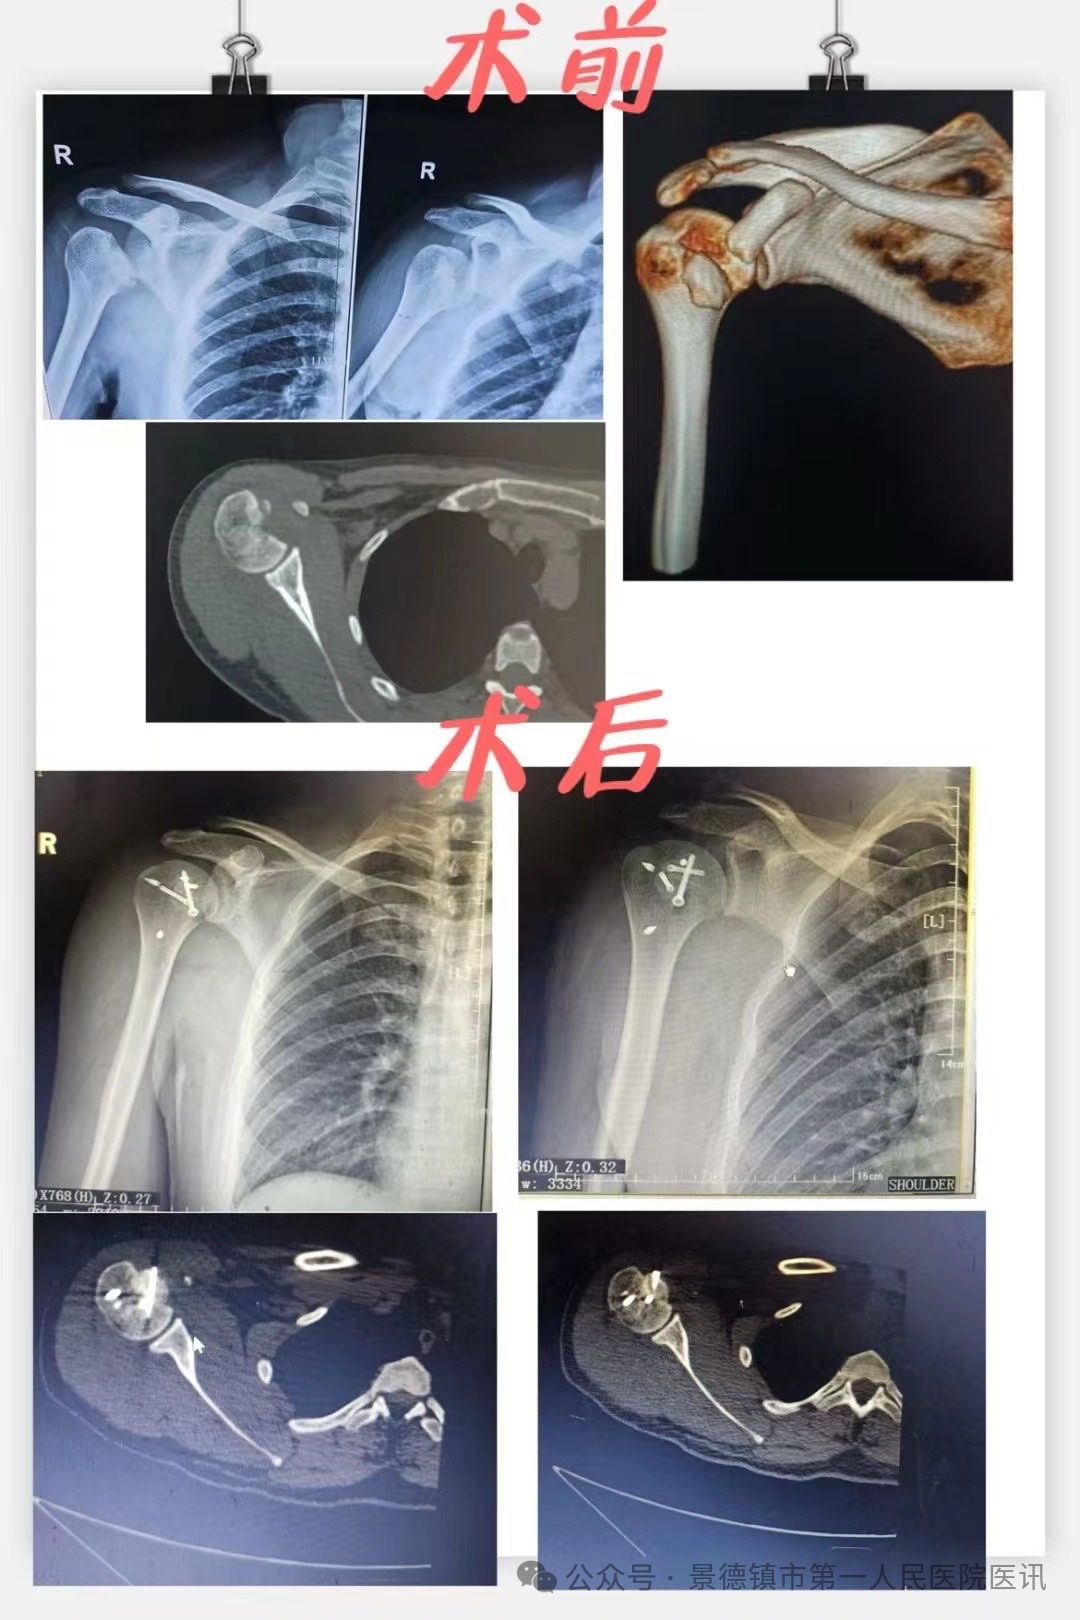

当前位置 :网站首页 > 医院文化近日,必赢242net官网骨科收治了一例罕见反Hill-Sachs 损伤患者。患者,30岁,因抽搐时倒地致右肩部受伤,活动受限9天。此前,患者曾在外院被诊断为肩关节后脱位并肱骨头骨折,并在麻醉下予以复位术,但情况并未好转,并且发生了脱位的情况,严重影响了患者的正常生活。

国庆假期第三天下午,骨科主任袁志峰在手术台上接到电话会诊,电话中告知在外院行右肩关节脱位行复位后易发再次脱位的年轻患者即将来求治,结合患者治疗经历和检查报告,骨科团队判断,患者为反Hill一Sachs损伤,合并肱骨小结节骨折、肩袖损伤、肱二头肌长头肌腱损伤。

考虑到患者年轻,肱骨头近1/2破裂,要尽可能重建关节的稳定性,同时又要减少对肱骨头血运的进一步破坏。袁志峰带领刘会文、付裕琪等手术团队反复讨论,大家均认为,手术内固定既要牢固可靠,又要不影响关节活动、减少对关节周围组织的刺激。因此,为患者制定了取髂骨结构性植骨移植+肱骨小结节骨折埋头钉固定+肩胛下肌损伤修复+肱二头肌长头肌腱切断固定的治疗方案。

患者遂于10月4日一早办理入院,急患者所急,并在第二日安排了手术治疗,骨科团队密切配合,为患者成功实施了手术。由于受损关节周围解剖结构复杂,有大量血管、神经通过。术中,手术团队缜密准备、精细操作。术中发现骨折处缺损大,遂切取髂骨用作移植物并夯实,复位肱骨小结节骨折并采取埋头钉固定,受损肩胛下肌予以带线铆钉修复,受损的肱二头肌长头肌腱予以切断并原位固定,历经1.5个小时,手术顺利实施。